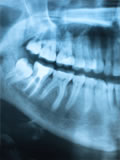

お口の中を調べ、レントゲン写真、歯周病検査、お口の中の写真撮影など、診断に必要な資料を撮らせて頂きます。